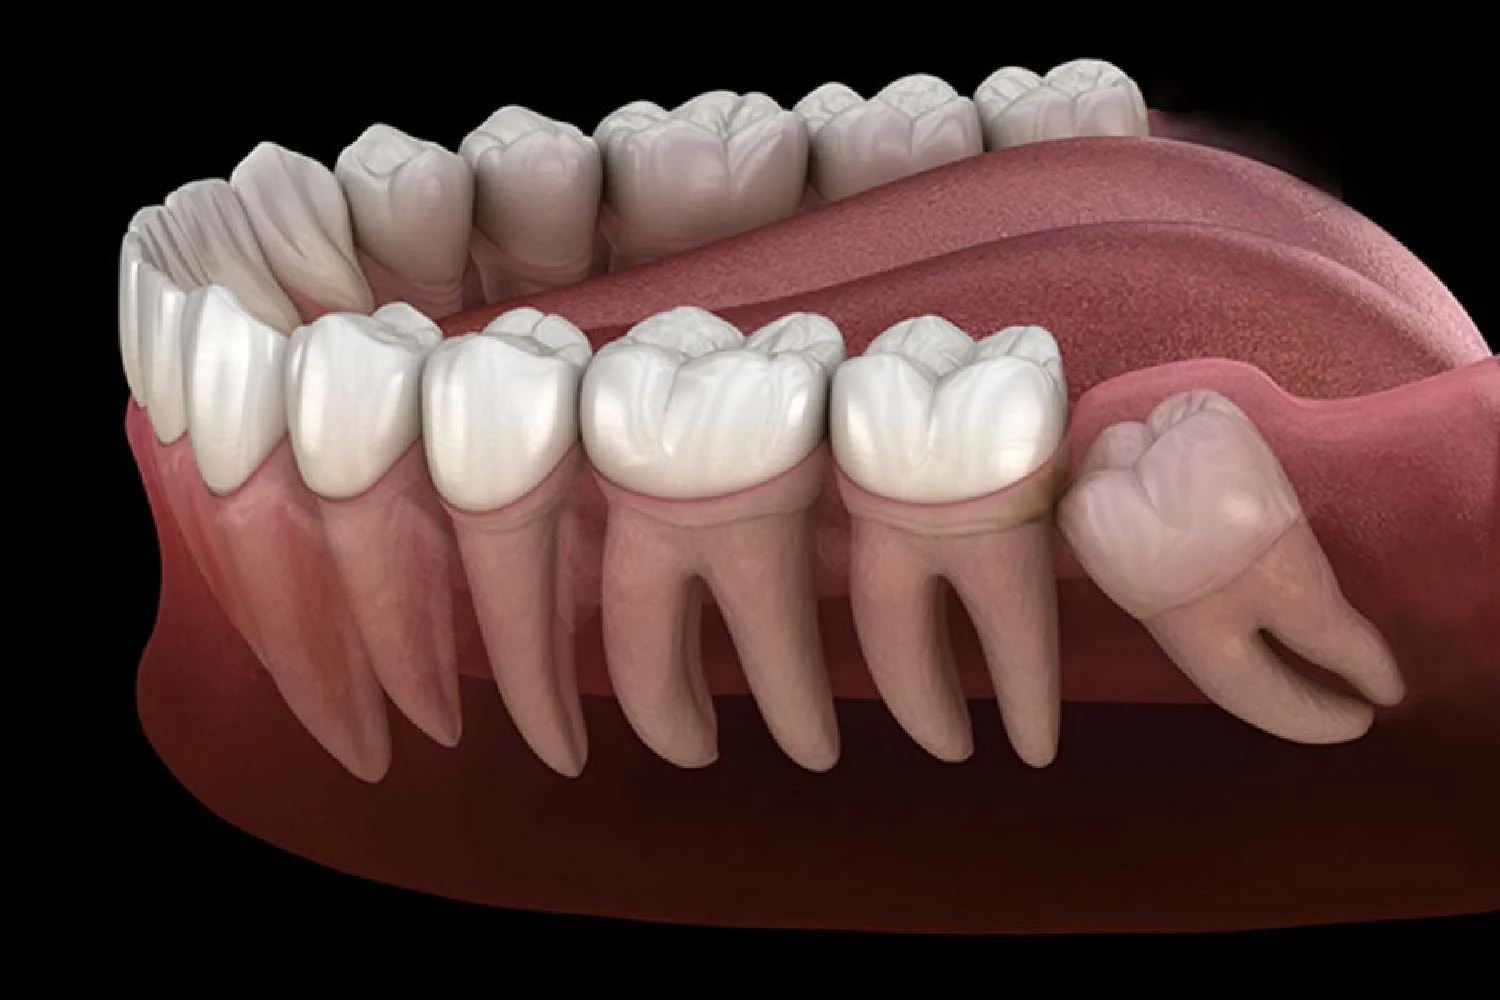

L’eruzione dei denti del giudizio può avvenire senza problemi, ma molto spesso è associata a disturbi e sintomi fastidiosi. Questo accade principalmente a causa della mancanza di spazio nell’arcata dentale, condizione che porta i denti del giudizio a crescere storti, inclinati o parzialmente inclusi nella gengiva.

- Crescita orizzontale o inclinata: il dente del giudizio spinge contro il secondo molare, causando dolore, carie o spostamento degli altri denti.

- Mancanza di spazio: l’arcata dentale troppo piccola non permette una corretta eruzione del dente, portando a inclusioni ossee.